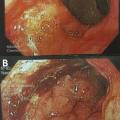

De même, une confusion fréquente est faite entre le type histologique ADCI et la linite gastrique. Cette dernière est définie macroscopiquement, en anatomopathologie, en endoscopie (fig. 2) ou en imagerie (fig. 3), par un aspect épaissi et rigide de la paroi gastrique. L’aspect de linite est fréquemment associé au type histologique ADCI, comme cela a été noté dans une série de 27 linites gastriques analysées par deux anatomopathologistes différents. P armi ces linites, 21 étaient des adénocarcinomes gastriques à cellules indépendantes et 6 d’autres types histologiques selon la classification de l’OMS. Après une troisième lecture des lames, il apparaissait que 4 tumeurs avaient un contingent minoritaire de cellules isolées (< 50 %) et 2 tumeurs étaient des adénocarcinomes tubulaires.3